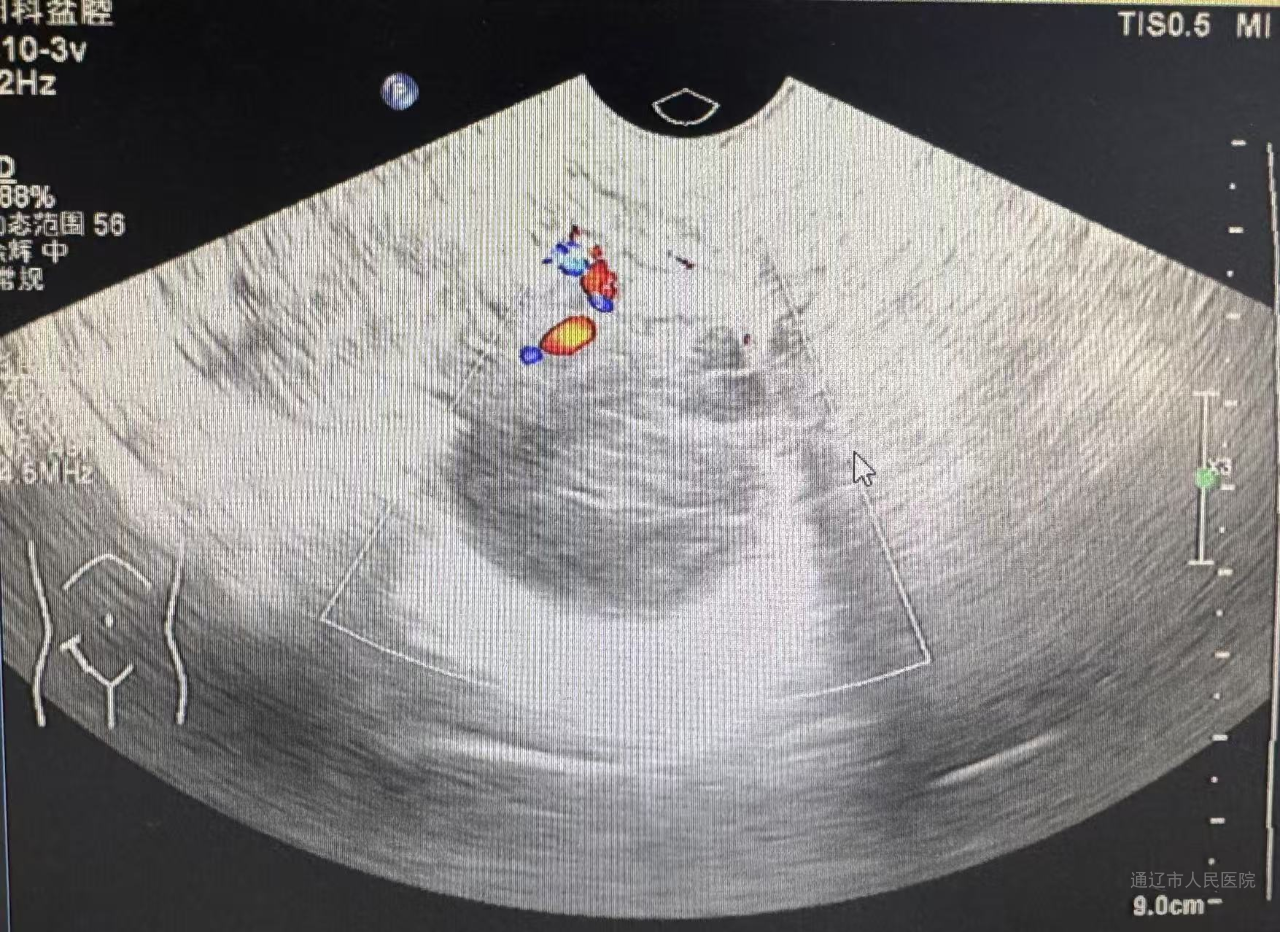

44岁患者左某某痛经10年加重,子宫增大如孕20周(18.3x12.3x17.4cm),经内分泌会诊诊断合并2型糖尿病性酮症、继发贫血及肿瘤标志物CA125>1000。经血管介入科行子宫动脉栓塞止血治疗,后经内分泌科调整血糖后再次转入我科行腹腔镜手术,此次手术依旧由白鹏来主刀,佟金荣、周所霞、程红岩协助,通过旋切器逐步缩小巨大子宫。快速病理结果显示为良性,术后第三天,患者术后第三天恢复良好。